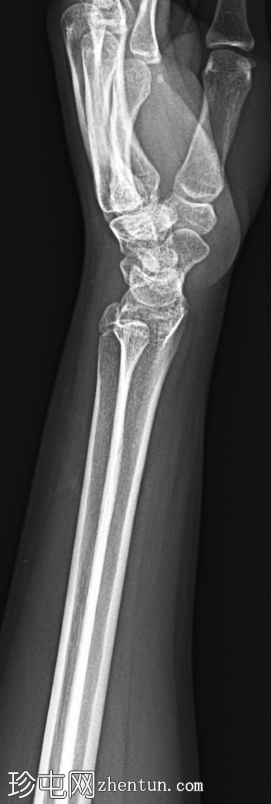

正位片

左腕正位X线片显示桡骨远端干骺端背外侧皮质轻微弯曲,无皮质破裂或移位。无明显成角畸形或尺骨骨折。关节间隙和腕骨排列正常。

最终诊断:桡骨远端干骺端轻微嵌插(弯曲型)骨折。